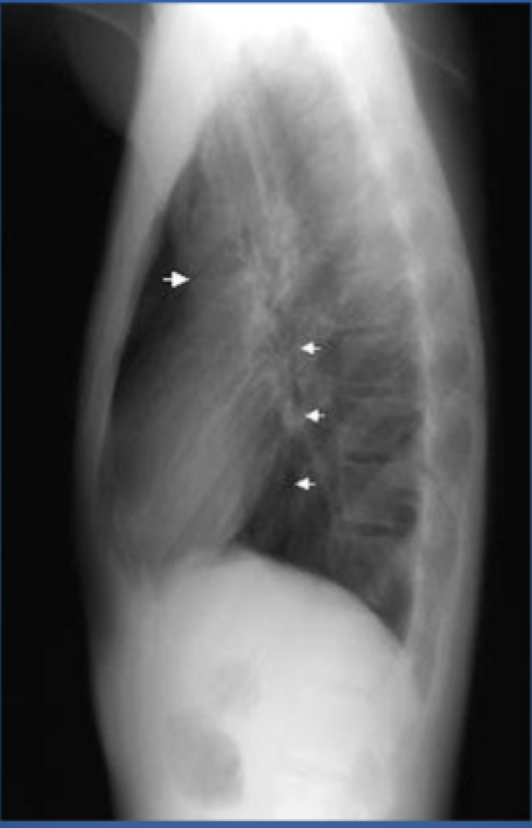

Loculated effusion CXR

-effusion may appear loculated (~mass/pseudotumor) if there are pleural adhesions